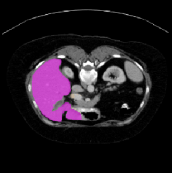

Figure 3 illustrates the specific segmentation results on the SABS dataset under Setting 1. Our model demonstrates higher accuracy in segmentation and effectively reduces unnecessary segmentation. Even under Setting 2, where the test class is entirely invisible to the model, our model performs well, as depicted in Figure 4. Given that SABS is a multi-organ dataset with many organs of small size, precise segmentation proves challenging. However, our model excels, particularly in the scenario of completely invisible classes, which closely resembles real-world conditions. Figure 4 highlights our model’s ability to accurately segment very small target organs, such as the right kidney. In contrast, the ADNet method fails to produce effective segmentation predictions, and other methods exhibit varying degrees of over-segmentation. On the CMR dataset, as shown in Table 2, our model generally outperforms others.